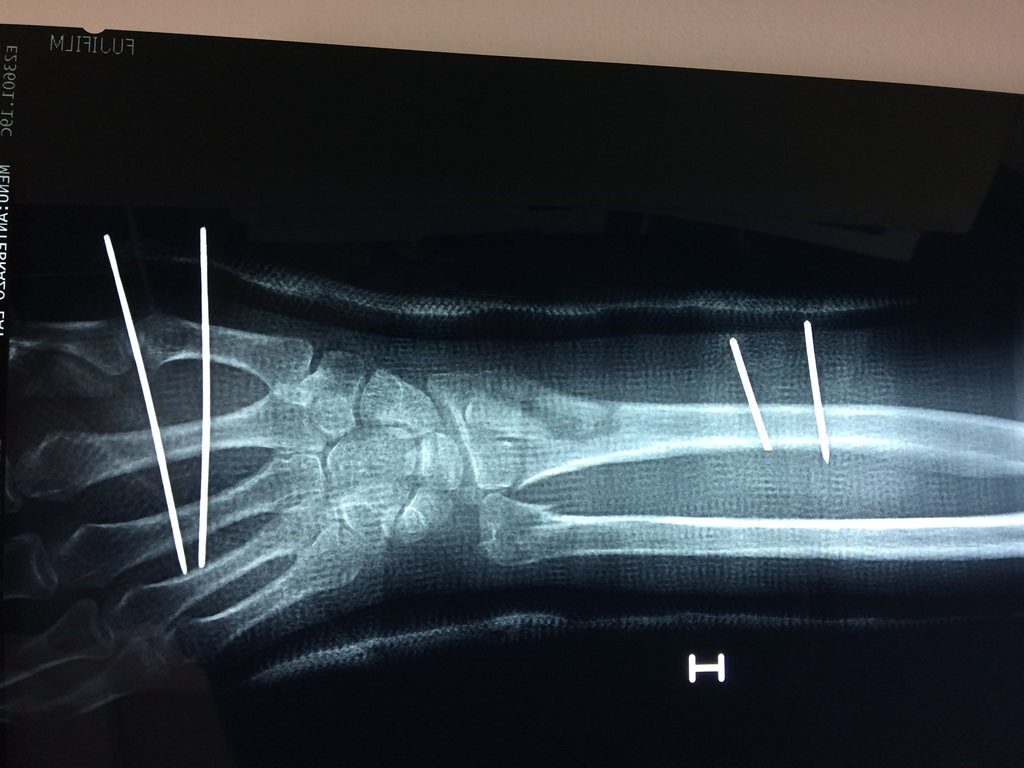

Cirugías de Hombros - Cirugías de Muñecas y Manos

Los procedimientos más comunes en cirugía de la mano son aquellos destinados a reparar traumatismos, incluyendo lesiones de tendones, nervios, vasos sanguíneos, y articulaciones; huesos fracturados; y quemaduras, cortes, y otros daños de la piel.